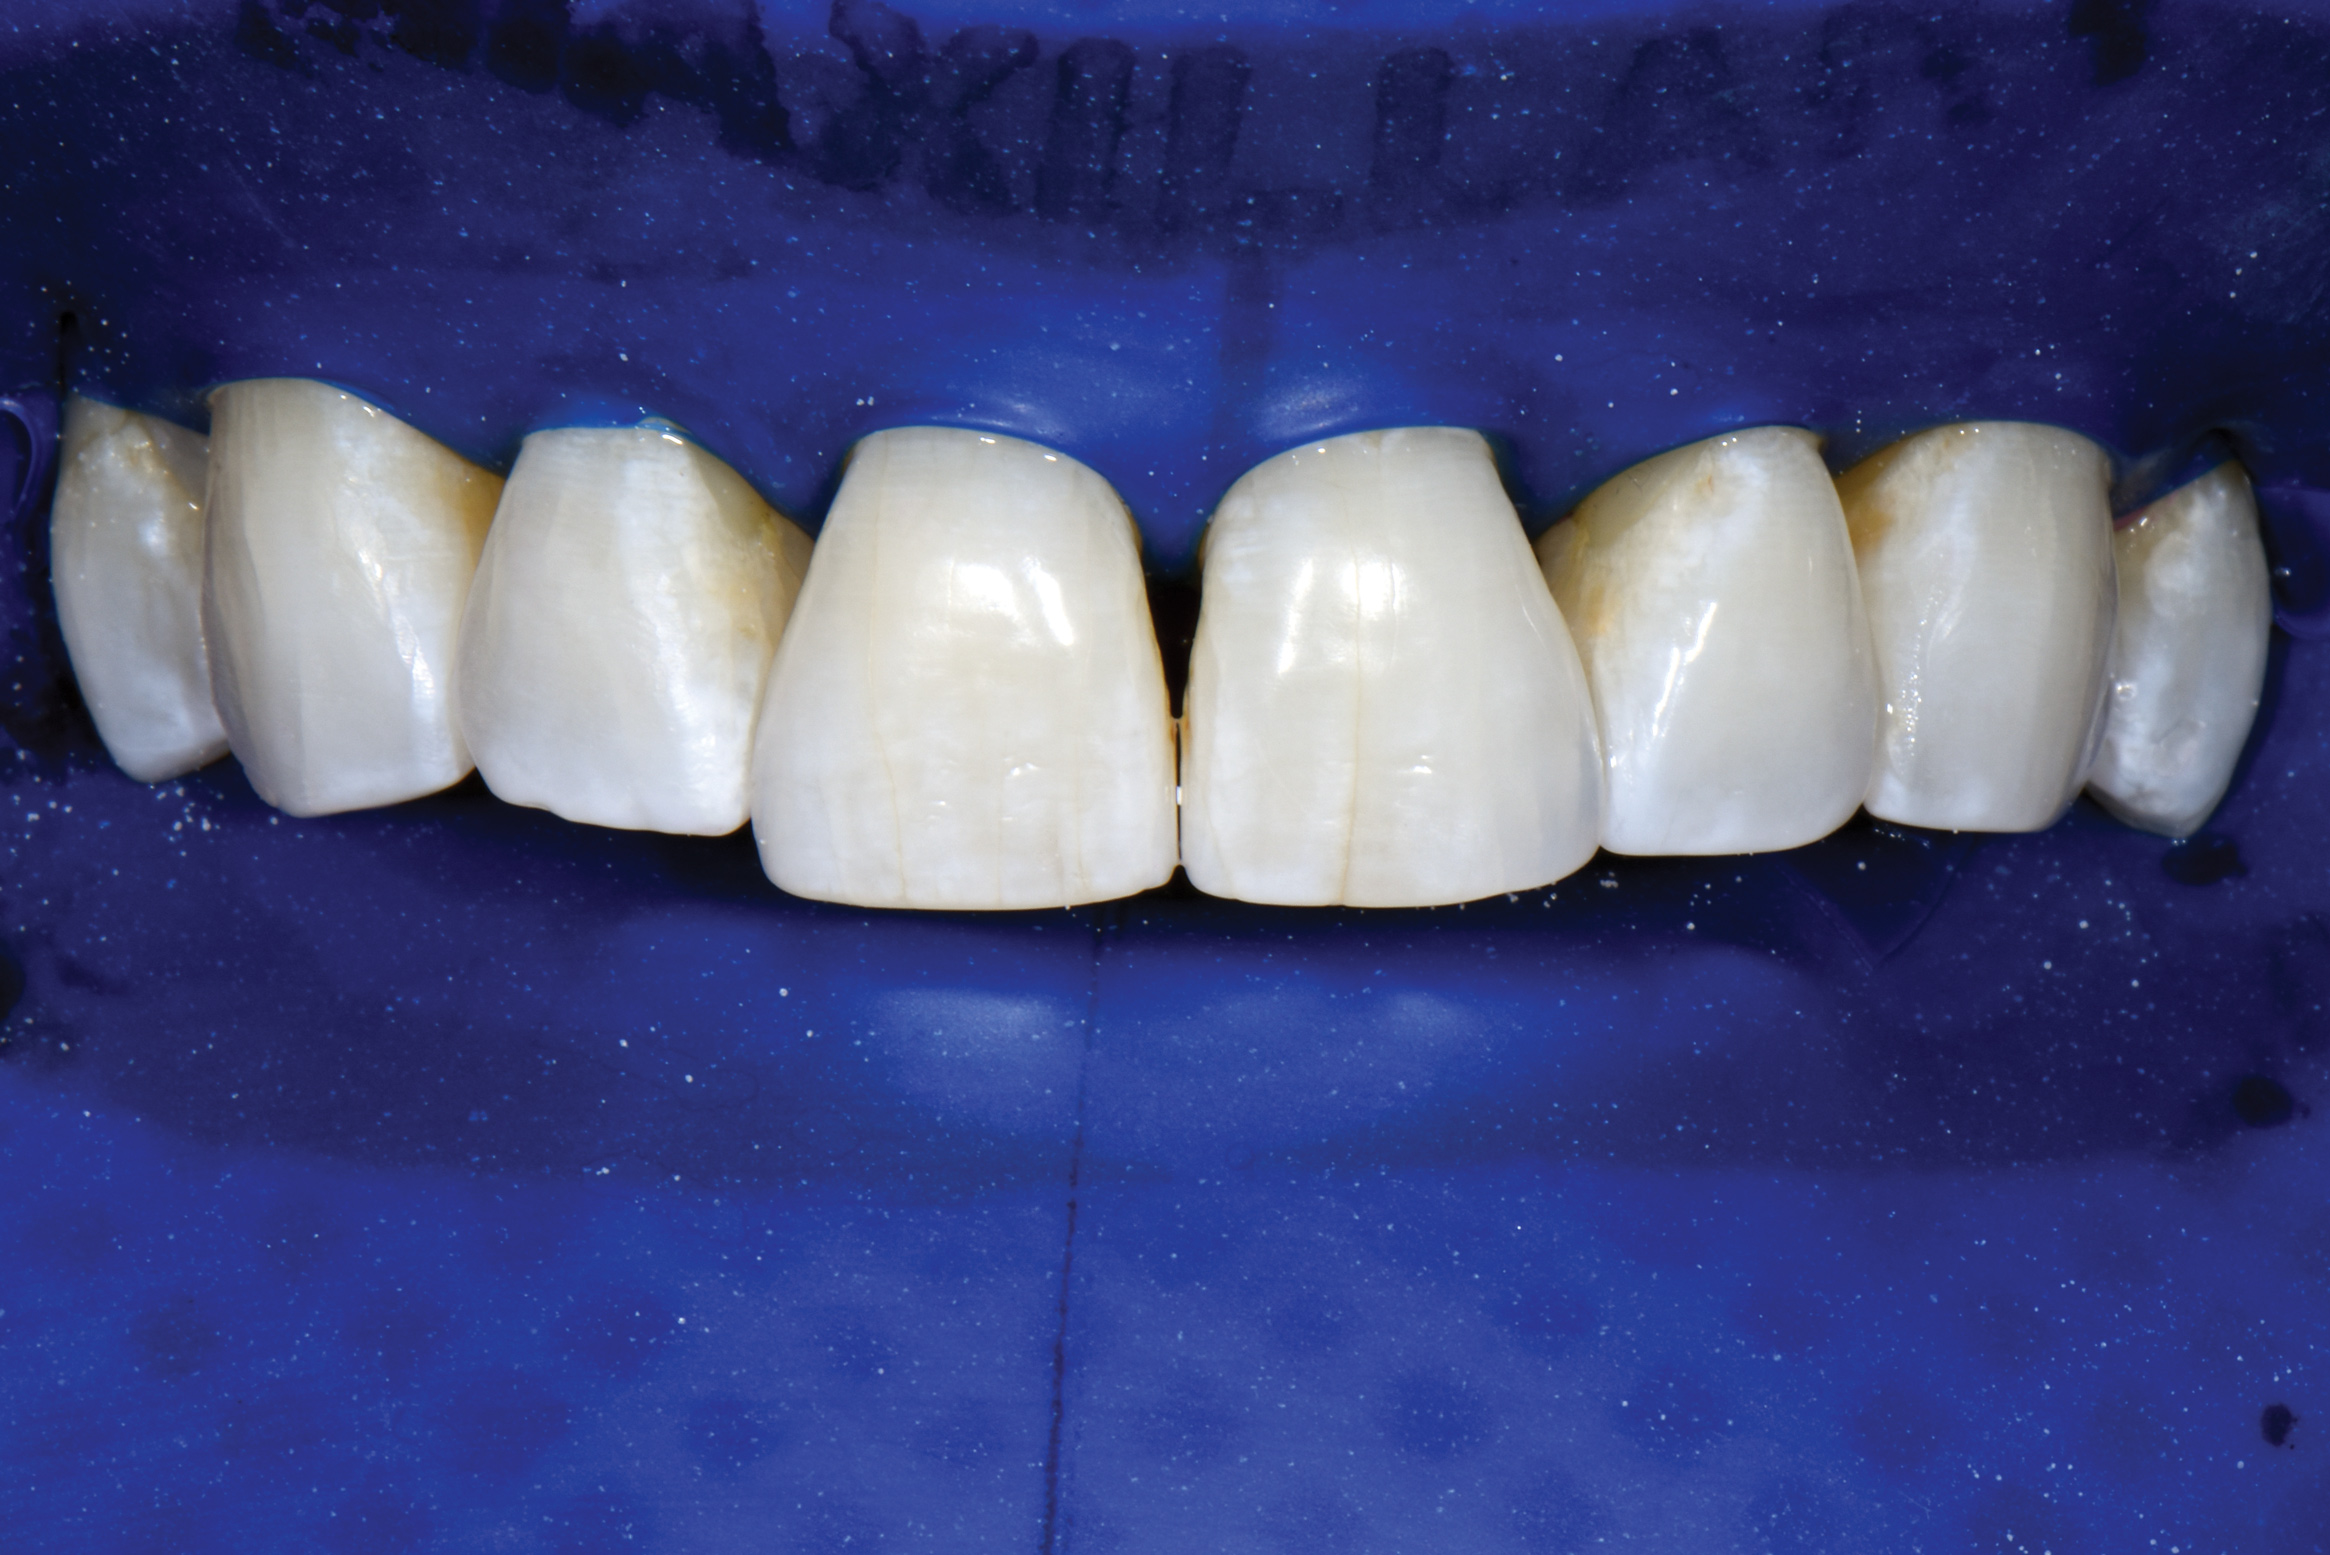

Fig 17. Application of two-tone disclosing solution to reveal biofilm.

Figure 17

Fig 18. Air abrasion with aluminum trihydroxide to remove biofilm.

Figure 18

Fig 19. Cleaned tooth surfaces after air abrasion prior to application of adhesive bonding resin composite to close black triangles.

Figure 19

Air abrasion with aluminum trihydroxide has been used as an adjunctive for tooth preparation to remove plaque, light calculus, undermined enamel, poorly bonded resins or liners, and soft-tissue tags prior to bonding. The rationale of biofilm removal before bonding is to remove any impediments to effective etching of enamel that may lead to reduced bond strength and microgaps that could contribute to future stain and leakage. Because biofilm can be difficult to visualize, a one-time application of a two-tone disclosing solution to dried teeth may help reveal biofilm and provide a visual cue for effective removal (Figure 17 through Figure 19). Some cleaning particles other than glycine or sodium bicarbonate can alter the enamel surface; therefore, reapplication of disclosing solution should be avoided as this may lead to risk of undesired staining of tooth structure.